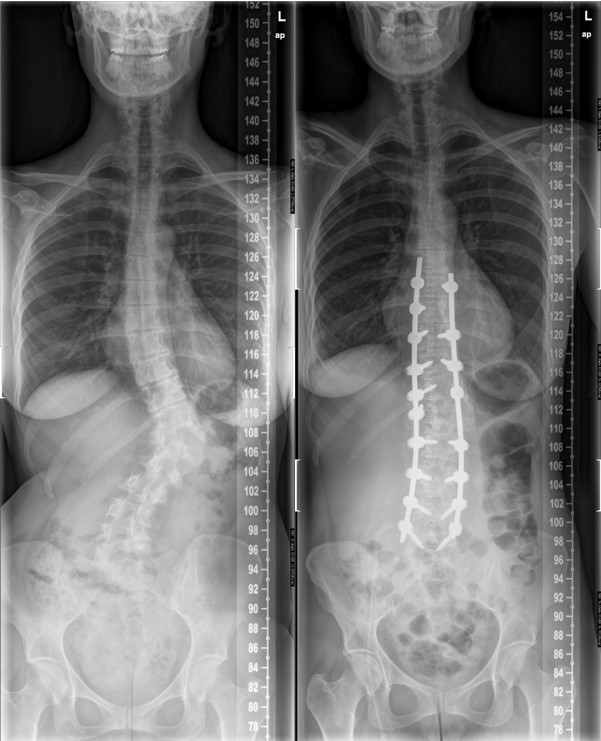

Foto 1 y 2: antes de la cirugía | Foto 3 y 4 después de la cirugía

En casos más graves, o en aquellos pacientes cuyos síntomas sean muy persistentes o deterioren de manera significativa su calidad de vida, la cirugía puede ser considerada como la mejor opción para corregir la curvatura y aliviar los síntomas.

Las técnicas quirúrgicas han avanzado significativamente, ofreciendo mayores tasas de éxito y recuperaciones más rápidas.

La cirugía se reserva para casos con deformidad, alteración importante de la imagen y discapacidad funcional y dolor resistente.

Consiste en corregir la deformidad y dar estabilidad a la columna. Muchos adultos con escoliosis pueden lograr una mejora significativa en sus síntomas y calidad de vida a través del tratamiento adecuado y prevenir que la escoliosis y los síntomas sigan progresando.

Es importante establecer expectativas realistas y entender que el objetivo del tratamiento es mejorar la función y reducir el dolor. Con la cirugía se puede corregir mucho la curvatura de la columna vertebral.